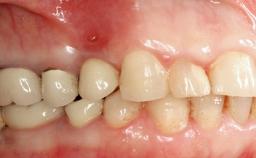

Peri-implant Carcinoma

Oral implants are highly successful and offer long-term benefits, especially in the rehabilitation of edentulous patients or patients with oral defects following ablative tumor surgery (Albrektsson and coworkers 1986), and also after radiation therapy (Schiegnitz and coworkers 2014). With the number of implants placed globally going into the millions, implant dentists have observed some rare adverse events. Although carcinogenesis around implants is an exceedingly rare phenomenon, we recently reported about 15 patients treated for carcinomas adjacent to implants at our clinical department over a period of fifteen years (Moergel and coworkers 2014). The following case represents a patient of this cohort; it discusses possible risk factors and makes suggestions for a recall schedule. A 70-year-old woman was referred to our outpatient department for evaluation of a rapidly growing macroscopic alteration of the mucosa in the left mandible.

Prosthesis Type FDP